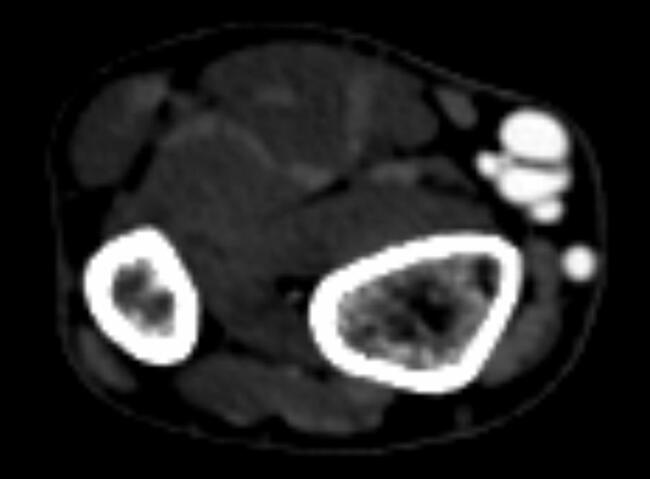

Twenty-two months after his catheterization, he was noted to have a mass on the volar aspect of his right wrist that was associated with pain on exertion (Figure 1). A thrill and bruit were present on physical exam. An arterial duplex and computed tomography angiography (CTA) demonstrated a 9 mm x 5 mm x 19 mm aneurysmal dilation of a radial artery branch associated with arteriovenous fistula (AVF) (Figure 2). An arteriogram was performed via the right femoral artery, which demonstrated an AVF from the distal radial artery into the radial veins with drainage into the cephalic vein. There was no evidence of pseudoaneurysm. Compression of the radial artery at the site of the AVF resulted in reconstitution of the distal radial artery via collateralization of the interosseous arteries and palmar arch. Additionally, there appeared to be a short segment venous occlusion with venous collateralization of arterial flow through cephalic and median antecubital vein tributaries. It is possible this venous obstruction was caused at time of coronary catheterization with a transradial compression band and contributed to the pressure gradient causing dilation of the arteriovenous fistula.